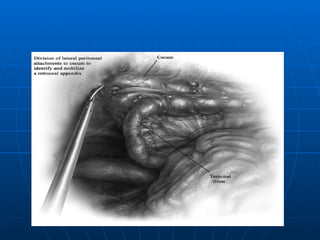

TRATAMIENTO CCONVENCIONAL INCISIONES  (estadío, dx certeza, posición y experiencia del cirujano). Transversa  (Rockey Davis): 3cms por debajo de cicatriz umbilical y se centra en la línea medio clavicular. Oblicua  (Mac Burney): Pasa por Pto. (cicatriz umbilical y EIAS) 1/3 por arriba y 2/3 por debajo. Paramediana Derecha  (Transrectales o Pararectales) Medianas  (más en mujeres).

TRATAMIENTO CONVENCIONAL APENDICECTOMIA: 1.- Localización del apéndice 2.- Transección del meso (arteria) 3.- Sección de la base (coprostasia) 4.- Manejo del Muñon( ligadura simple, inversión o combinación de ambos,pto. En Z o jareta) APENDICECTOMIA RETROGRADA PLASTRON APENDICULAR (Muñon libre + Drenaje) PERITONITIS DIFUSA (Lavado Peritoneal) APENDICE NORMAL

TRATAMIENTO CONVENCIONAL APENDICECTOMIA:1.- Localización del apéndice 2.- Transección del meso (arteria) 3.- Sección de la base (coprostasia) 4.- Manejo del Muñon( ligadura simple, inversión o combinación de ambos,pto. En Z o jareta) APENDICECTOMIA RETROGRADA PLASTRON APENDICULAR (Muñon libre + Drenaje) PERITONITIS DIFUSA (Lavado Peritoneal) APENDICE NORMAL